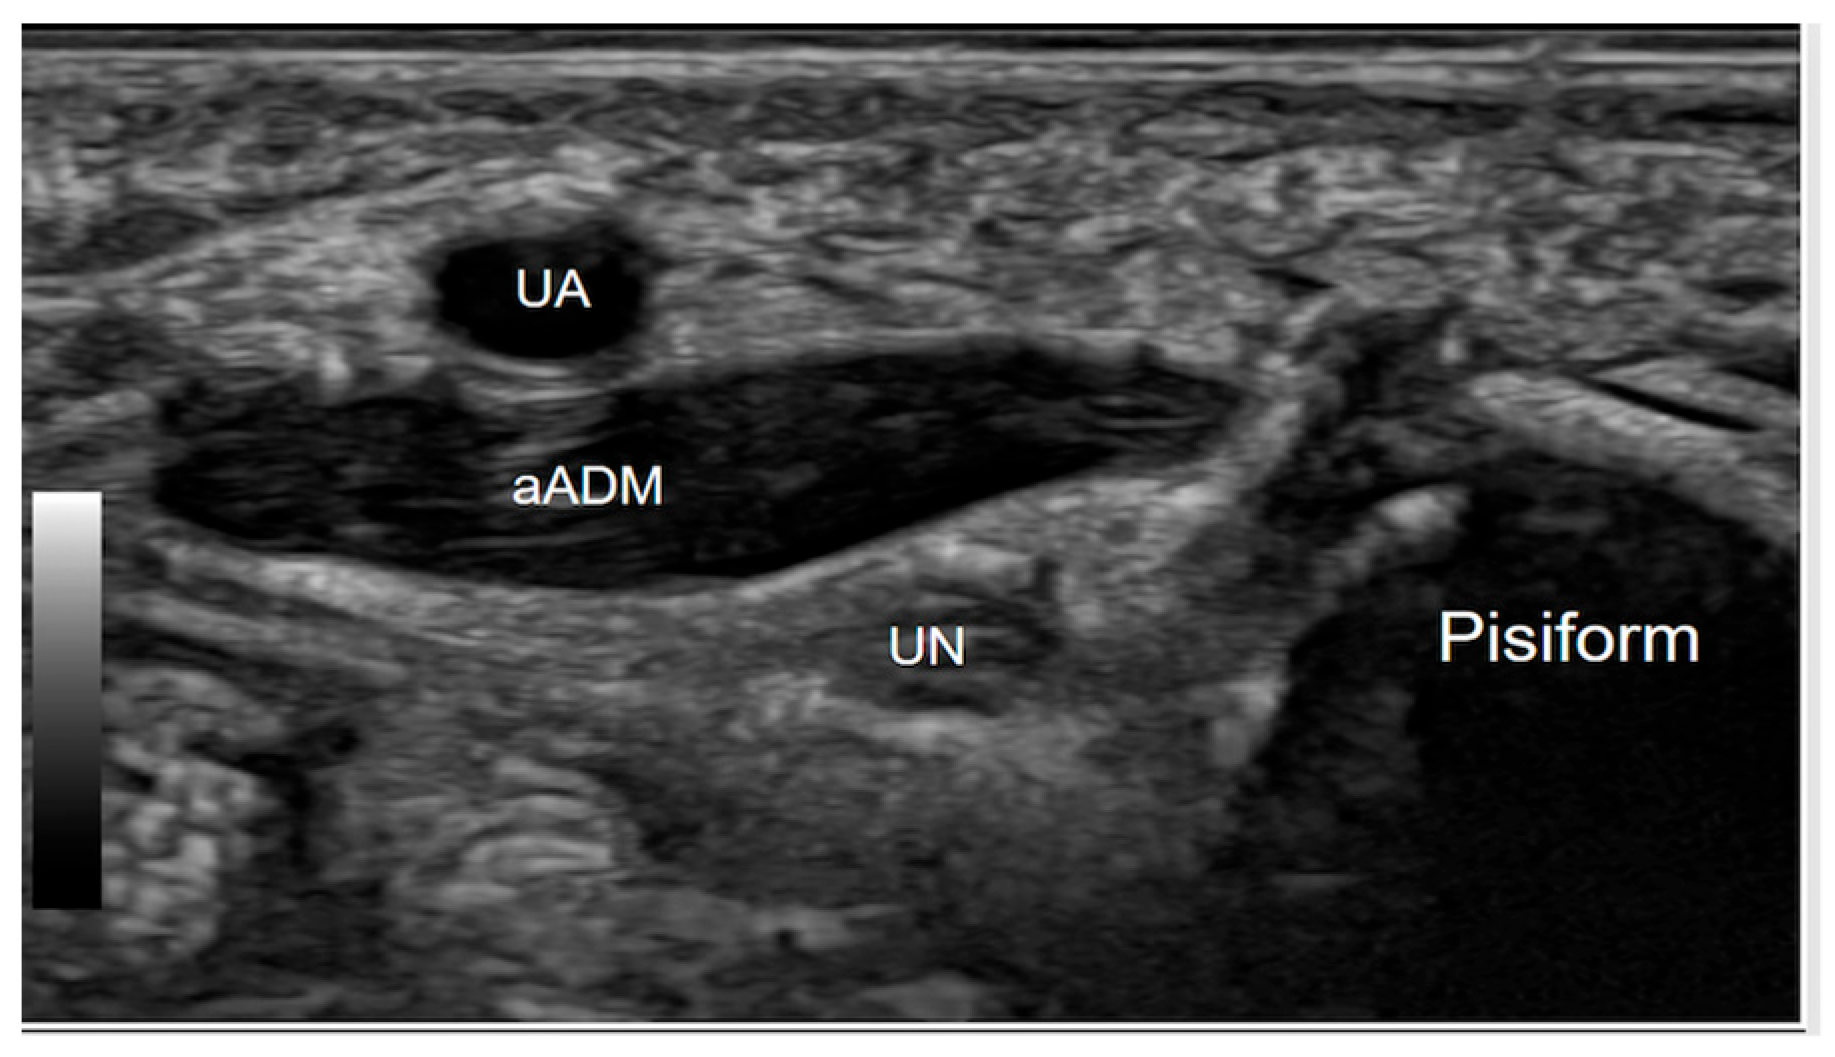

3.1. Ultrasound Technique and Anatomy

4.1. Accessory Abductor Digiti Minimi